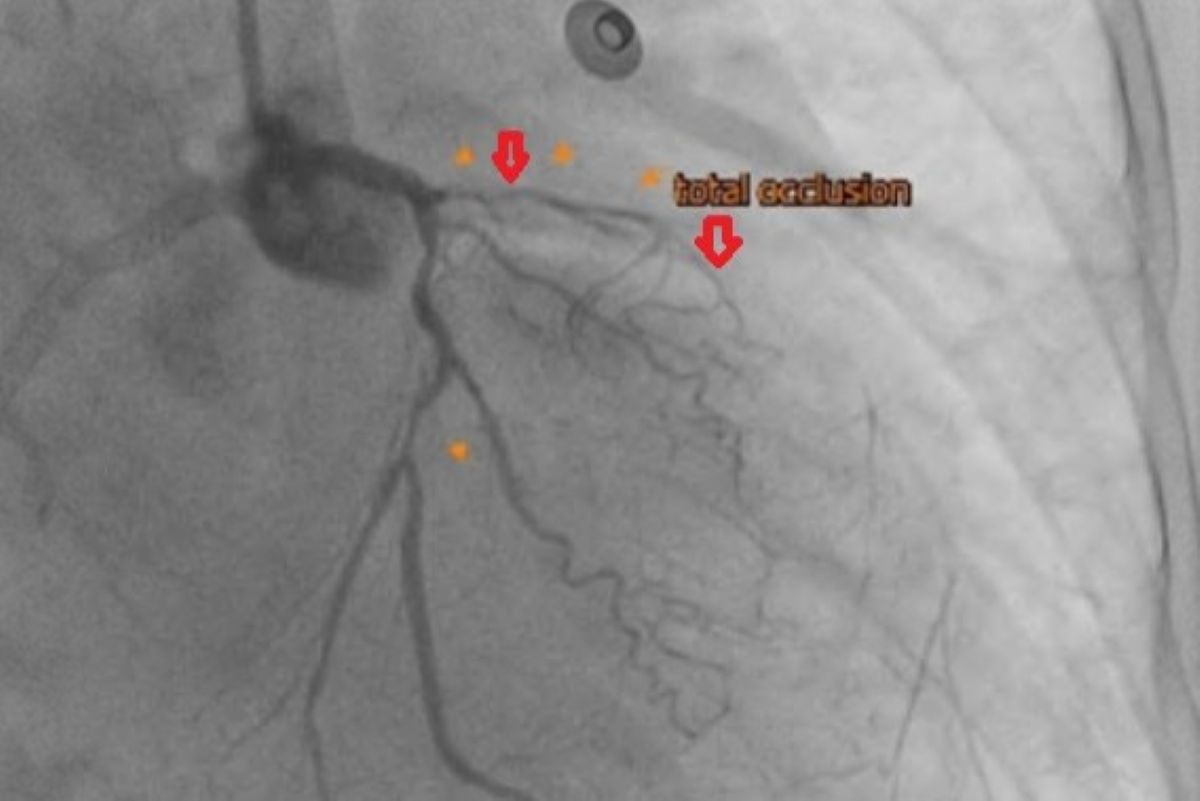

63歲的陳奶奶長年患有三高,三個月前出現呼吸越來越喘、胸悶不適等症狀,來到台北慈濟醫院心臟血管科就診並收治入院。心導管檢查發現其左前降支合併完全阻塞左迴旋枝狹窄,心臟超音波發現左心室收縮功能不到30%(正常為50-60%),診斷為缺血性心肌病變,即冠狀動脈阻塞導致的慢性心臟衰竭,因此照會心臟血管外科楊凱文醫師。後續透過心臟核磁共振,楊凱文醫師評估病人仍有可挽救的心肌,經過心臟內外科跨團隊和患者充分討論後,決定採取複合式冠脈血流重建的治療策略。由楊凱文醫師執行達文西微創冠狀動脈繞道手術,以左內乳動脈為繞道血管,重新供應左前降支的血流,後續是需要再由心臟血管科醫師進行心導管疏通左迴旋枝的狹窄。術後病患左心室收縮功能明顯進步,目前於門診定期回診追蹤。

冠狀動脈疾病的診斷需結合多項檢查綜合評估,除了透過心導管檢查確認血管狹窄位置與嚴重程度,也會輔以心電圖與心臟超音波了解心臟節律與收縮功能是否存在異常。在心臟收縮功能較差的病患,則可能藉由核磁共振評估是否還有可挽救的心肌存在。在治療選擇上有心導管支架置放及外科手術,前者適用於單一血管狹窄且情況不嚴重或病人手術風險過高;後者則有傳統開胸及達文西微創手術兩種,適用於多條血管嚴重狹窄甚至阻塞的情形。有時則可以採取所謂複合冠脈血流重建的方式,顧名思義是一種結合了心臟外科的「微創冠狀動脈繞道手術 (MIDCAB)」與心臟內科的「經皮冠狀動脈介入治療 (PCI)」的治療方式,旨在融合兩者優點,為複雜的冠心病患者提供更佳的血流重建。